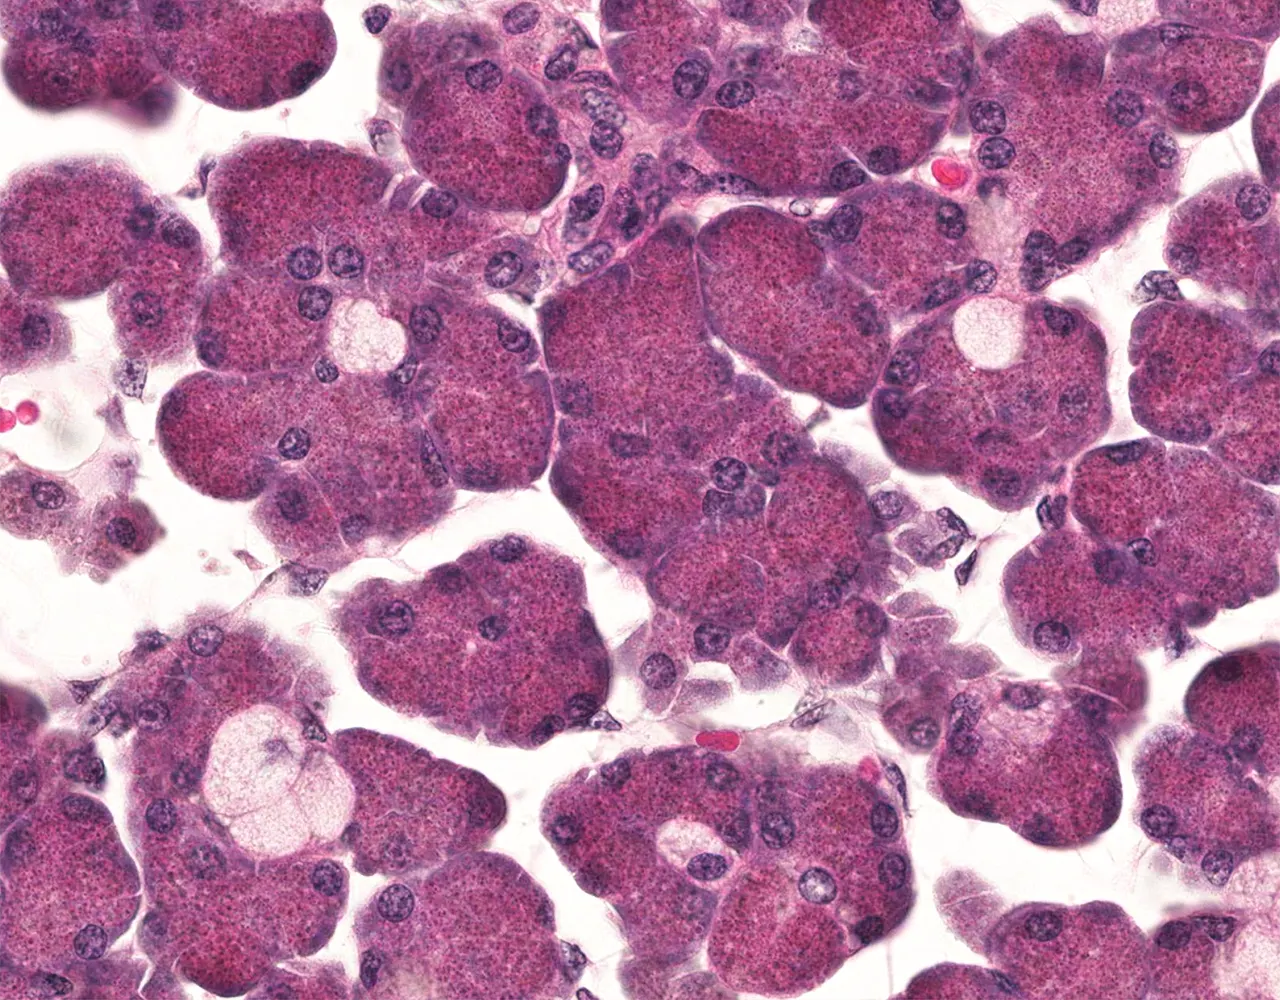

- Microscopically, the functional structure of a salivary gland consists of secretory acini and a duct system.